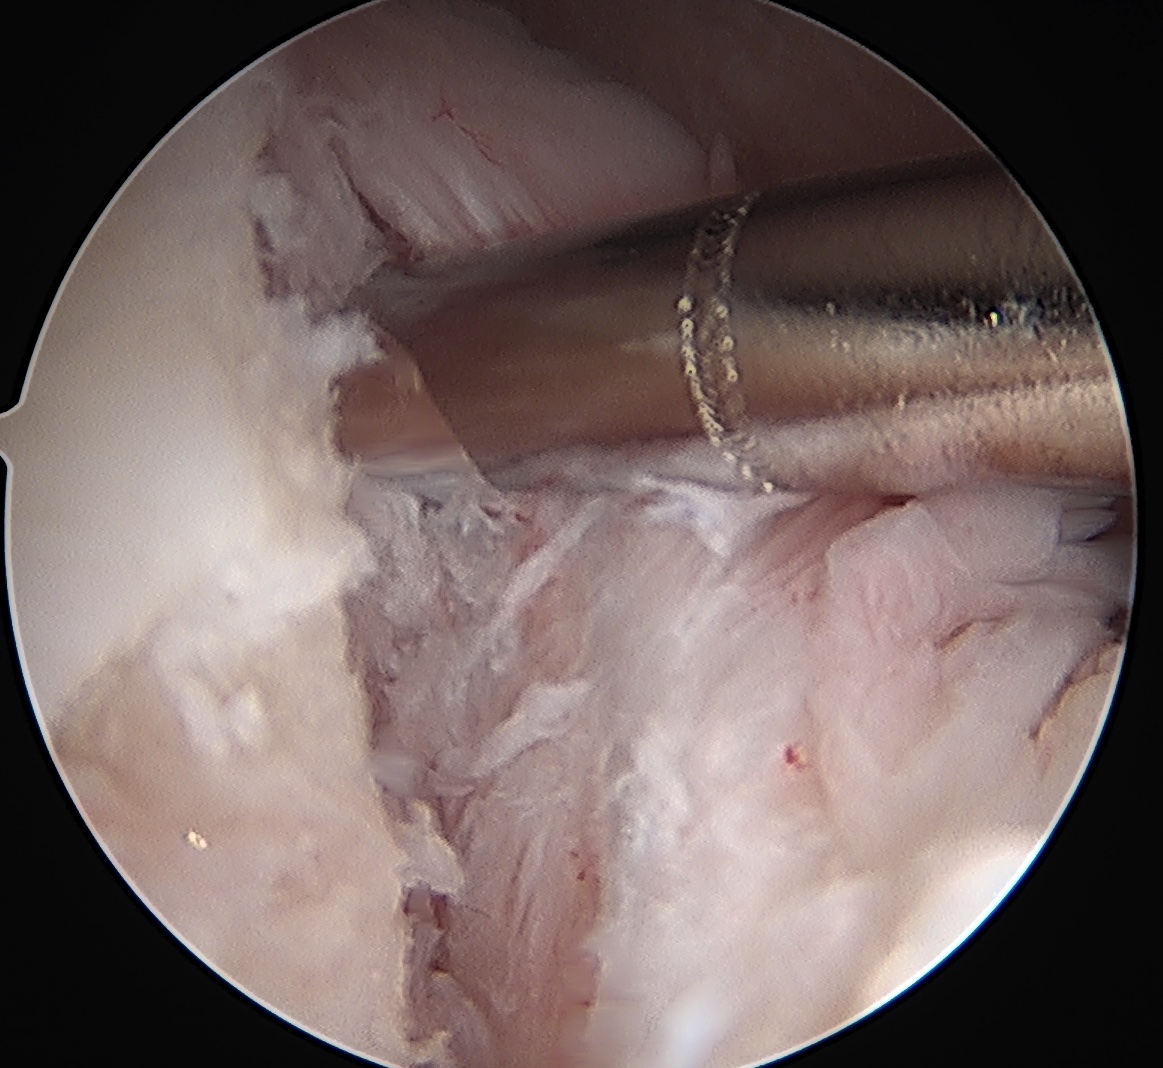

Posterior labral repair

Posterior capsular plication

Arthroscopic posterior labral repair / capsular plication

Technique